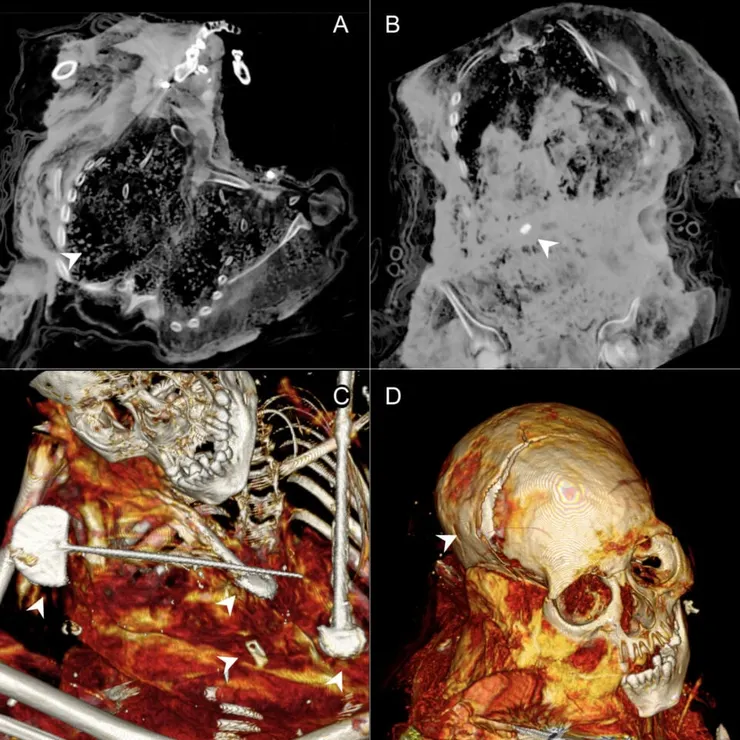

索查表示:「這些遺骸來自高海拔火山地區,那裡低溫、乾燥的氣候與缺乏微生物的環境有利於軟組織的保存。電腦斷層掃描揭示傳統檢測方法無法發現的細節。這使我們能夠識別出已知的首例人為製作的卡帕科查受害者木乃伊,以及這些木乃伊化兒童身上存在的諸多損傷與病理變化。」

分析結果顯示,這四名兒童均死於頭部重擊。其中一名受害者是一名8歲女童,他患有腦內血腫。他也表現出包括食道擴張與肺部鈣化在內的恰加斯病(Chagas disease)特徵性病變。在被稱為「安帕托夫人(Lady of Ampato)」或「胡安妮塔(Juanita)」的木乃伊身上,研究人員發現了胸部與骨盆的損傷。他的臉部於2023年進行重建。

最出乎意料的發現與編號為「安帕托4號(Ampato 4)」的木乃伊。電腦斷層掃描顯示,其裹屍布內的解剖結構扭曲,骨骼碎片缺失,腹腔內有石塊與疑似紡織品碎片。研究人員認為這是死後人為介入的證據。